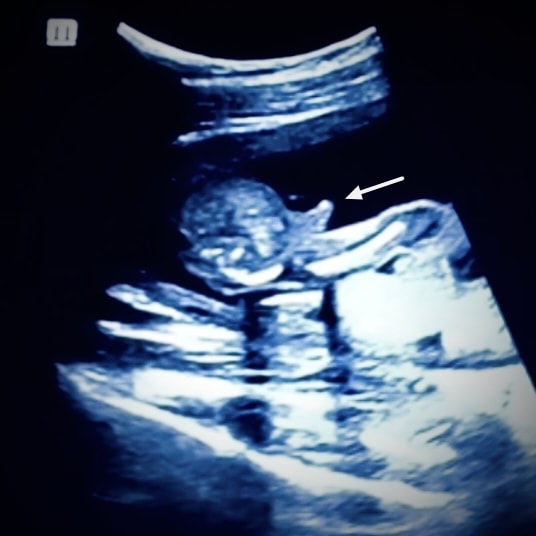

День X (17 недель 5 дней) - Мальчик или девочка?

Проснулась я рано, в предвкушении УЗИ, решила что узнаю пол с мужем на приёме). Отправились как и в прошлый раз (на 13 неделе) в клинику Медис к Маклаковой Елене Ивановне. Очень волнительно было, попросила супруга всё заснять на телефон. Малыш не спал, немного поикал, покрутился, попинался, ручкой поводил🥹. Первым делом, конечно, узист навела на орган, спросила мужа ну кто там? Он сразу понял, заулыбался, но мне не сказал, мало ли я передумаю и захочу гендер пати). Я сказала, что хочу знать сейчас, он несколько раз повторил, так как я переспрашивала - мальчик). А потом сама посмотрела на экран и поняла, что тут сложно ошибиться)).

ЗАКЛЮЧЕНИЕ УЗИ:

Срок беременности 17 нед 5 дн. Имеется живой плод в головном предлежании, петли пуповины вокруг шеи нет (так как наш мальчик очень активный я переживала что он запутается в пуповине, теперь я спокойна)).

ФЕТОМЕТРИЯ:

Бипариетальный размер головы 42,8 мм. Окружность головы 149,4 мм. Окружность живота 127,6 мм. Длина бедренной кости правой 23,7 мм левой 23,7 мм. Размеры плода соответствуют 17 нед 5 дн. Предполагаемая масса плода 212 г. По анатомии плода всё в норме, отклонений в развитии нет.

Плацента расположена по задней стенке матки на 3 см выше внутреннего зева. Толщина плаценты: нормальная, 20 мм. Структура плаценты: расширение МВП. Степень зрелости плаценты: 0 степень ( 0-I до 32 нед, II -до 36 нед).